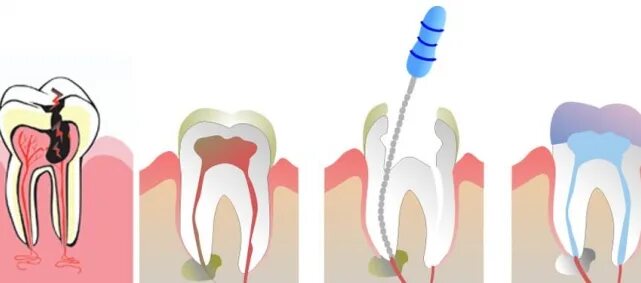

Воспаление зуба после удаления нерва